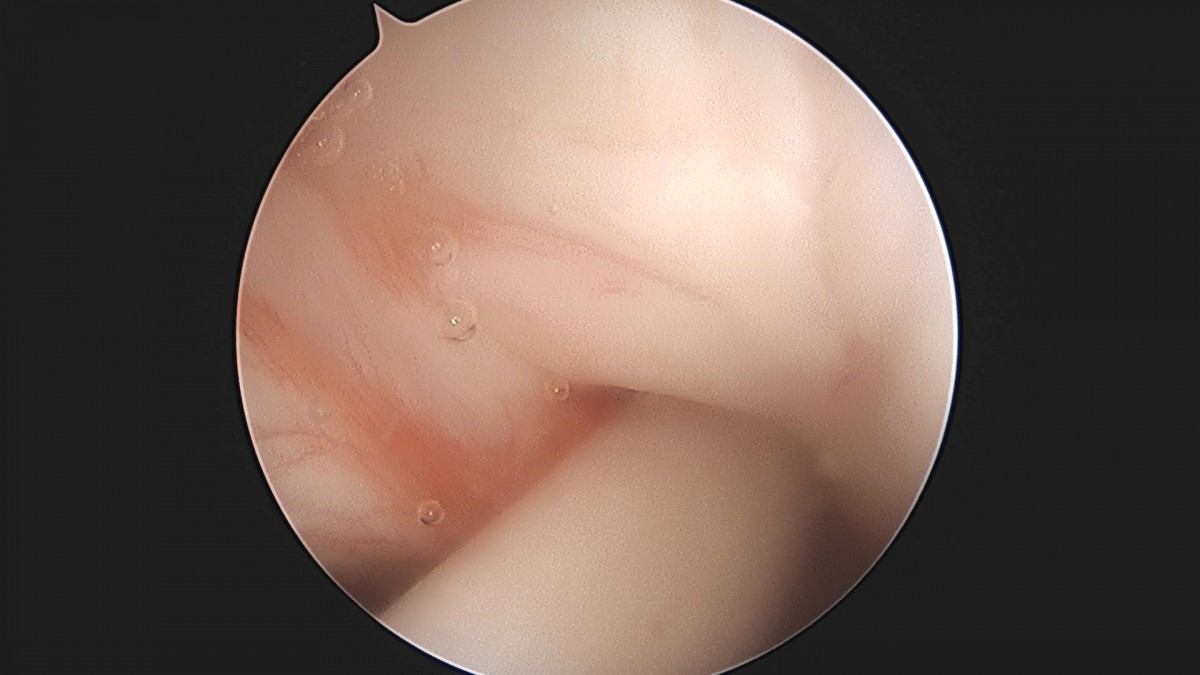

이재상원장님 어깨 견봉성형술 박선O 환자

작성자 최고관리자 댓글 0건 조회 2,239회 작성일 22-07-12 12:33